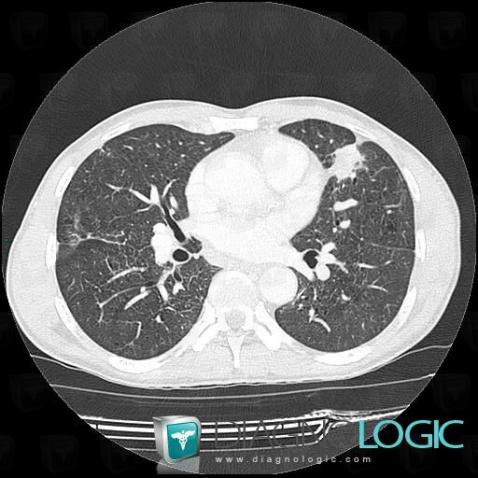

Silicosis, Pulmonary parenchyma, CT

Here is the specific information in the key image above:

- Diagnosis Silicosis (link to Pneumoconiosis), Location(s) Pulmonary parenchyma, with gamuts Solitary pulmonary mass